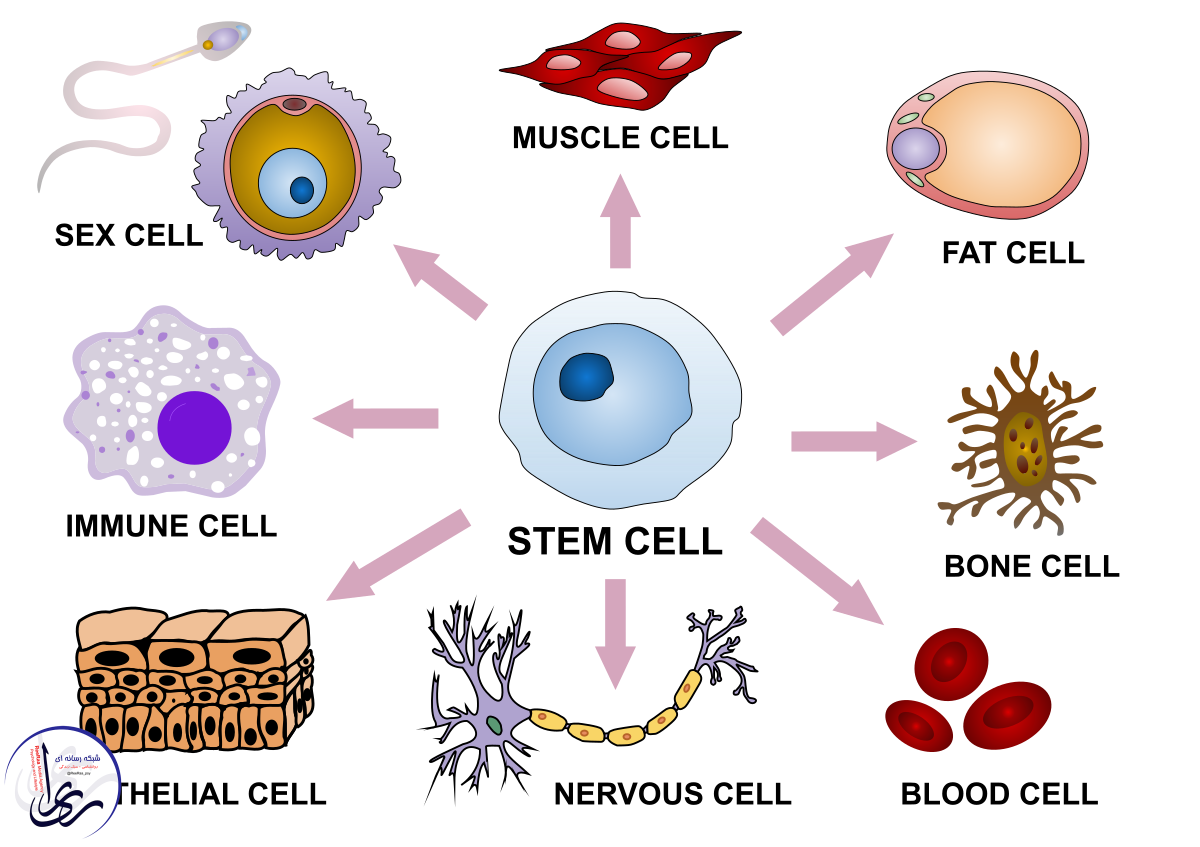

- یکی از درمانهای ایدهآل برای عضلات آسیب دیده، این است که با تزریق سلولهای بنیادی خودشان تقویت شوند.

یکی از درمانهای ایدهآل در حوزه پزشکی ترمیمی برای بیمارانی که عضلات آنها به خاطر کمبود اکسیژن آسیب دیده، این است که با تزریق سلولهای بنیادی خودشان تقویت شوند.

یکی از درمانهای ایدهآل برای عضلات آسیب دیده، این است که با تزریق سلولهای بنیادی خودشان تقویت شوند.

این باور وجود داشته که سلولهای بنیادی به دست آمده از بافت چربی خود بیمار میتوانند عوامل لازم را برای به وجود آمدن رگهای خونی جدید در عضله آسیب دیده فراهم کنند.

سلول های بنیادی

مارنی بوپارت، از نویسندگان این پژوهش گفت: مزیت اصلی سلولهای بنیادی در ترمیم بافت، لزوما توانایی آنها در ترمیم بافت از دست رفته نیست، بلکه این سلولها میتوانند عوامل رشد و سیتوکینها را نیز برای کمک به این روند منتشر کنند.

این روش، مزایای قابل توجهی دارد به خصوص هنگامی که سلولها در بافتهای آسیبدیده، بیمار یا سالخورده به کار میروند.